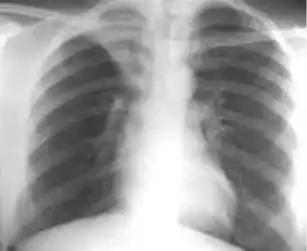

1. Infiltrate or consolidation - Opacification of airspaces within the lung parenchyma. Consolidation or infiltrate can be dense or patchy and might have irregular, ill-defined, or hazy borders.

Dense homogenous opacity in right, middle and lower lobe of primary pulmonary TB. -